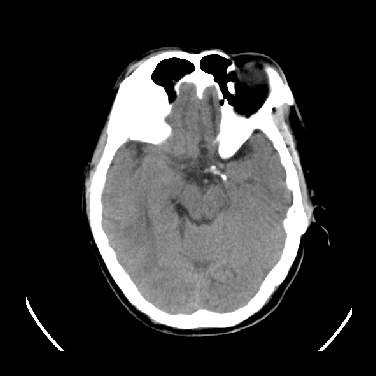

标题: CT16999:男,45岁,左侧肢体乏力1周。请会诊 [打印本页]

男,45岁,左侧肢体乏力1周。ex:胸片示:两肺团块状、斑片状密度增高影,其内可见小空洞。支纤镜、经皮肺穿示:干酪样物。

考虑囊变转移瘤

结合病史考虑结核瘤,不除外转移瘤。

结合病史考虑结核性脑炎脑膜炎,伴脑脓肿形成,囊变转移瘤不除外